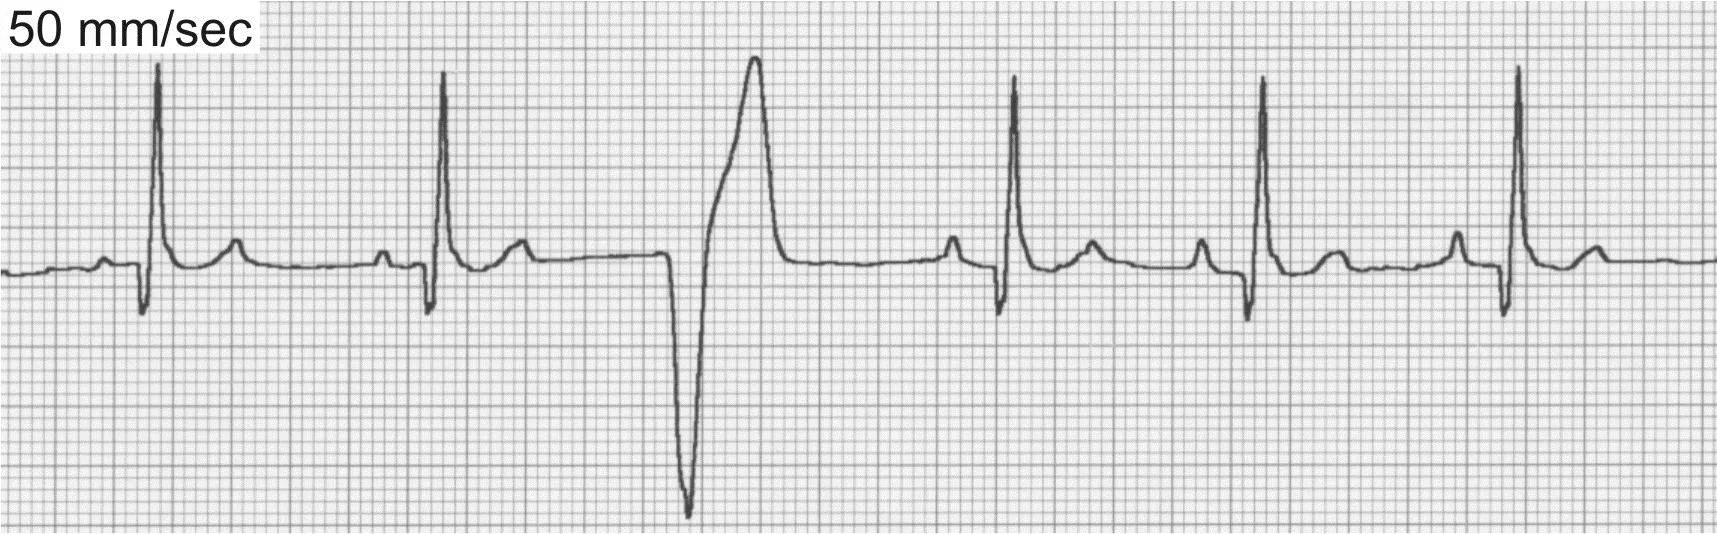

Accelerated Idioventricular Rhythm

Also known as slow ventricular tachycardia (Figure 4), this is a unique form of ventricular tachycardia typified by slow heart rates (dogs, 70–150 bpm). The rate of the accelerated idioventricular rhythm is usually within 10 to 15 beats of the normal sinus rate, and control of the heart rhythm alternates between the two sites. Because the rate of the idioventricular focus is slow, there is little hemodynamic consequence and patients generally remain asymptomatic. These rhythms are commonly seen with noncardiac disease and also in dogs with traumatic myocarditis and neurologic disease. Specific treatment of an accelerated idioventricular rhythm is rarely indicated and should be directed toward underlying causes.

ECG of accelerated idioventricular rhythm, or slow ventricular tachycardia